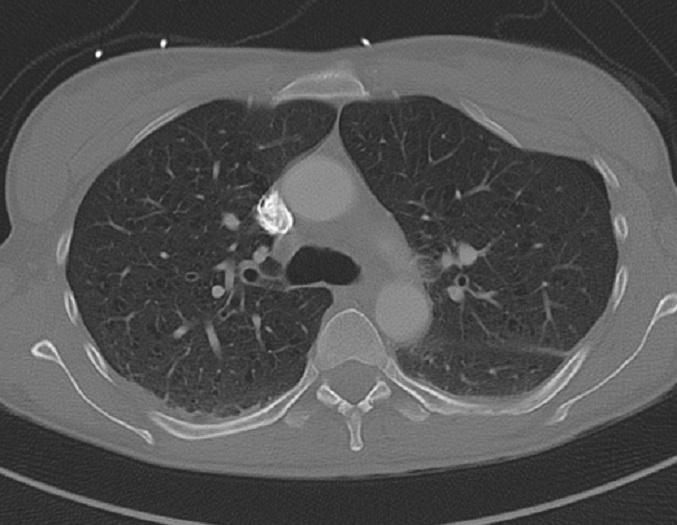

Image radiologique TDM en

coupe axiale fenetre parenchymateuse d'une

fracture de plusieure de cote anterieure ( 3th -9th

) en formant " flait chest " de la poitrine . |